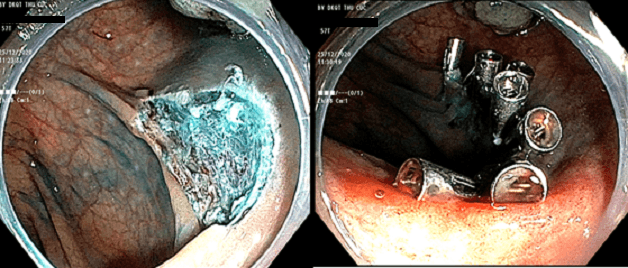

– Cắt hớt niêm mạc EMR hoặc cắt tách dưới niêm mạc ESD: Áp dụng đối với polyp kích thước từ 1cm, tổn thương lớn diện chân cắt rộng phải kẹp nhiều clip để khép miệng tổn thương.

Hình ảnh polyp đại tràng sau cắt và được kẹp clip tại chân cắt.